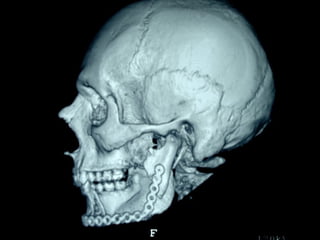

Angiografía carotídea

Sierra de GigliSierra de Gigli

Luxación de hemimandíbula

Pieza quirúrgica

Plantilla flexible para dar forma previa al implante

Se respetó el cóndilo para anclar la prótesisSe respetó el cóndilo para anclar la prótesis

Límite tumoralLímite tumoral

Area de lisis ósea a nivel de la línea

Miliodes que contracturó los músculos

Milohioideo y pterigoideo interno

Dificultando la deglución y determinando

Trismus importante.

Pieza en proceso de examen por histopatología

Dr. Ismael Espejo Plascencia Patólogo

48 horas de post-operatorio